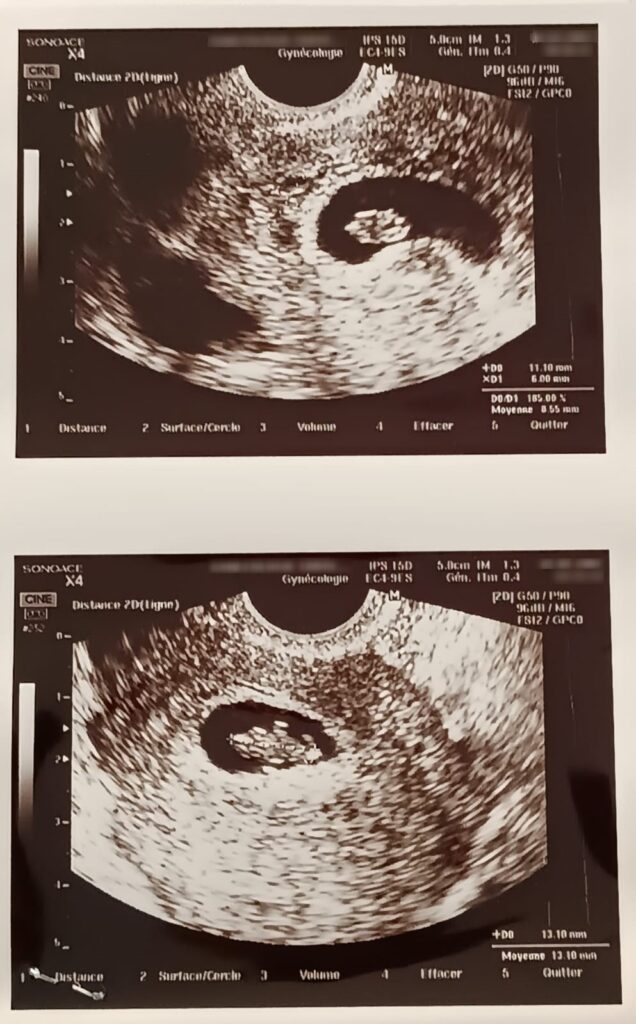

J’attends ce rdv avec impatience ! J’ai tellement hâte de savoir comment se passe l’évolution de notre embryon !